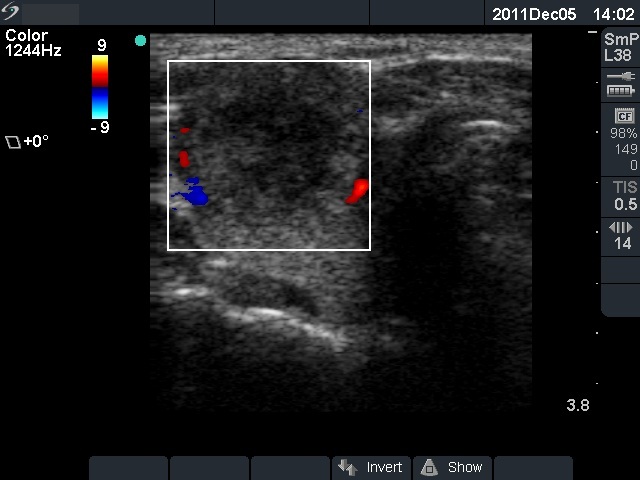

Ultrasonography: The right thyroid was echonormal and contained several small, insignificant lesions. There was a hypoechogenic lesion with blurred borders in the central and in the ventro-medial part of the left thyroid with increased intranodular blood flow.

The ultrasound pattern of de Quervain's thyroiditis and that of papillary cancer are very similar: a hypoechogenic lesion with blurred borders are found in both cases. They differ in vascularization statistically but the vascular pattern has only limited practical significance. In the acute phase of de Quervain's thyroiditis the vascularization is generally decreased but even in this case the situation was the opposite. The finding of not one but multiple hypoechogenic areas favored the possibility of subacute thyroiditis.